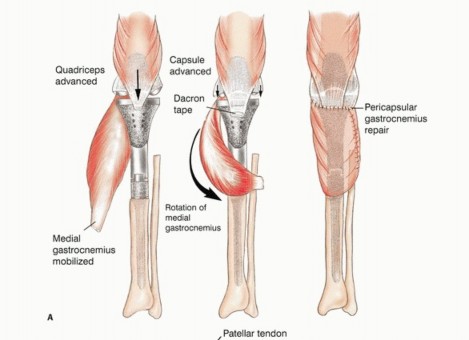

آلية المد

يتم استئصال موقع ارتباط آلية المد (الوتر الرضفي عند حديبة قصبة الساق) بشكل كتلة واحدة مع قصبة الساق القريبة. إعادة بناء هذه الآلية أمر ضروري لوظيفة الطرف المصاب. بدون إعادة بناء فعالة، قد يعاني المريض من ضعف كبير في القدرة على مد الركبة، مما يؤثر على المشي والحركة.

دور سديلة العضلة التوأمية الإنسية (Gastrocnemius Rotational Flap)

يُعد استخدام سديلة العضلة التوأمية الإنسية (عضلة الساق) عاملاً رئيسياً في تحقيق تغطية كافية للأنسجة الرخوة للطرف الصناعي واستعادة وظيفة آلية المد. تُنقل هذه العضلة لتدور إلى الأمام لتغطية الطرف الصناعي، مما يقلل بشكل كبير من خطر العدوى ومضاعفات الجروح، وهو ما كان يمثل تحدياً كبيراً في الماضي. يؤكد الأستاذ الدكتور محمد هطيف على أن هذه التقنية أصبحت إجراءً روتينياً وموثوقاً لضمان تغطية الطرف الصناعي وتقليل معدل العدوى ونخر السديلة والبتر الثانوي.

تفاصيل الإجراء الجراحي للحفاظ على الطرف

تُعد جراحة الحفاظ على الطرف في أورام قصبة الساق القريبة إجراءً معقداً يتطلب خبرة جراحية عالية وتخطيطاً دقيقاً. يقوم الأستاذ الدكتور محمد هطيف بتطبيق أحدث التقنيات لضمان استئصال الورم بشكل كامل وإعادة بناء الطرف بأمان وفعالية. تتضمن الجراحة ثلاث خطوات رئيسية:

- استئصال الورم: إزالة الجزء المصاب من قصبة الساق والأنسجة المحيطة به مع هامش أمان كافٍ.

- إعادة بناء العيب الهيكلي ومفصل الركبة: زرع طرف صناعي أو طعم عظمي لاستبدال الجزء المستأصل.

- إعادة بناء آلية المد وتغطية الطرف الصناعي بالأنسجة الرخوة: استخدام سديلة العضلة التوأمية لضمان التغطية والحفاظ على وظيفة الركبة.